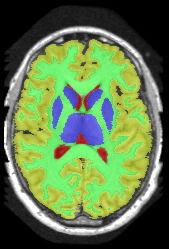

| ground truth | a-exp[7, 8] | QPBO [25, 8] | ours |

We extend [8], which introduced HINTS for arbitrary trees. In [8] a-expansion (a-exp) [7] was used to optimize the multi-label formulation of HINTS, but it often results in bad local minima due to complexities of interaction constraints, e.g. Fig.2. The contribution of [8] is a binary multi-layered HINTS formulation. They use high-order data terms, which are not easy to convert into unary and pairwise potentials for arbitrary trees. Their algorithm’s global optimality guarantee depends on the tree at hand. Only trees that do not yield frustrated cycles [25] have this guarantee, but this is not immediately obvious for any given tree. In [8], non-submodular binary energy implied by frustrated cycles were addressed by QPBO [25]. In practice, QPBO produces only partial solutions for most trees, see Figs. 2, 15 and 17.

3 Optimization

In Section 3.1 we introduce our Path-Move algorithm and in Section 3.2 we show which interaction constraints Path-Move could optimize. The authors in [8] showed that HINTS is non-submodular for a general tree and they used either QPBO or a-exp for optimization. Unfortunately, QPBO does not guarantee to label all pixels and we observed that in our experiments, see Fig. 2. The a-exp algorithm [7] is guaranteed to label all pixels but prone to weak local minima, Fig. 2.